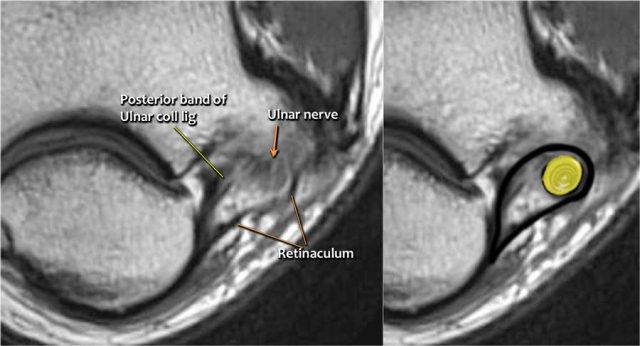

Ulnar nerve

Ở đây chúng ta thấy dây thần kinh trụ nằm trong ống trụ.

Bó sau của dây chằng bên trụ tạo thành sàn của ống, trong khi mạc hãm tạo thành trần của ống.

Đầu tiên hãy quan sát các hình ảnh.

Bệnh nhân này bị bệnh lý thần kinh trụ.

Nguyên nhân là gì?